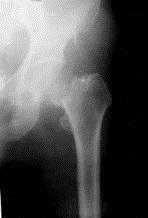

问题 病历摘要: 患者××,女性,70岁,不慎跌倒致伤左髋部后疼痛、活动障碍2天。查体:左下肢呈屈髋屈膝及外旋畸形,右下肢活动时左髋部疼痛,左足跟和大粗隆有叩击痛。 以下诊断哪些是正确的? 提示:该患者X线片见图

选项 A、左股骨头基底部骨折 B、左股骨颈骨折头下型 C、左股骨颈骨折Garden Ⅳ型 D、左股骨粗隆间骨折 E、左股骨颈骨折Garden Ⅱ型 F、左股骨颈骨折Garden Ⅲ型 G、左股骨颈骨折Garden Ⅰ型

答案 BF